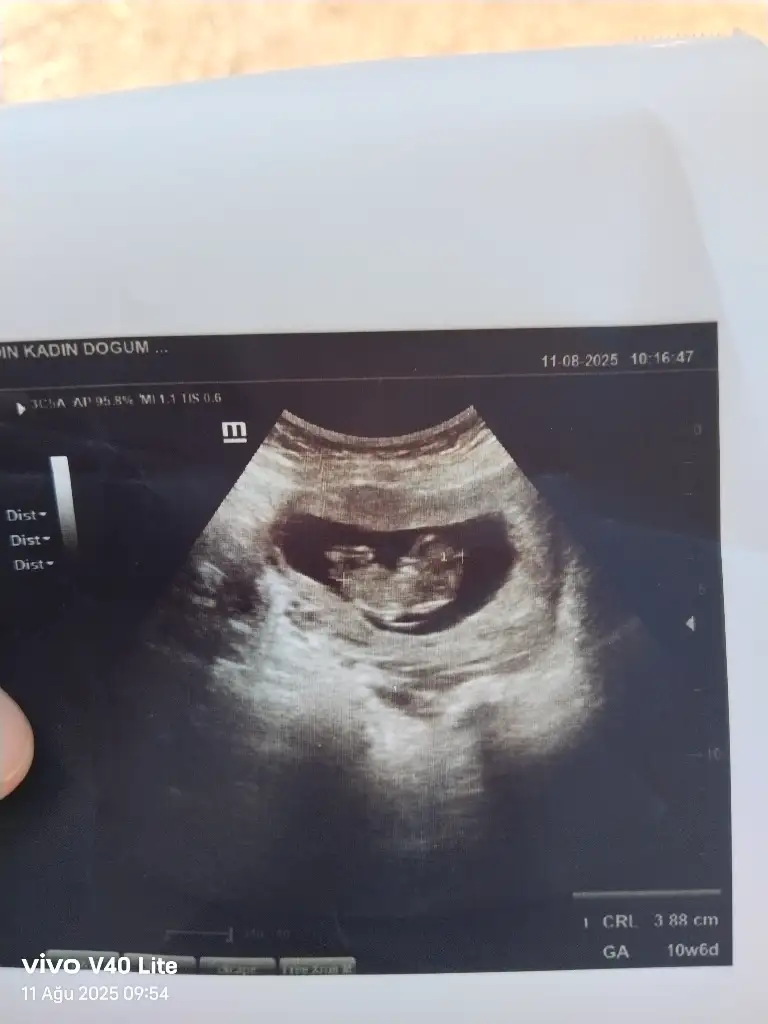

Merhaba hanımlar cinsiyet tahmini yapabilir misiniz 11 hafta

Eklentiler

• IMG_20250723_160814.webp

16,5 KB · Görüntüleme: 52

• IMG_20250723_160822.webp

13,9 KB · Görüntüleme: 50